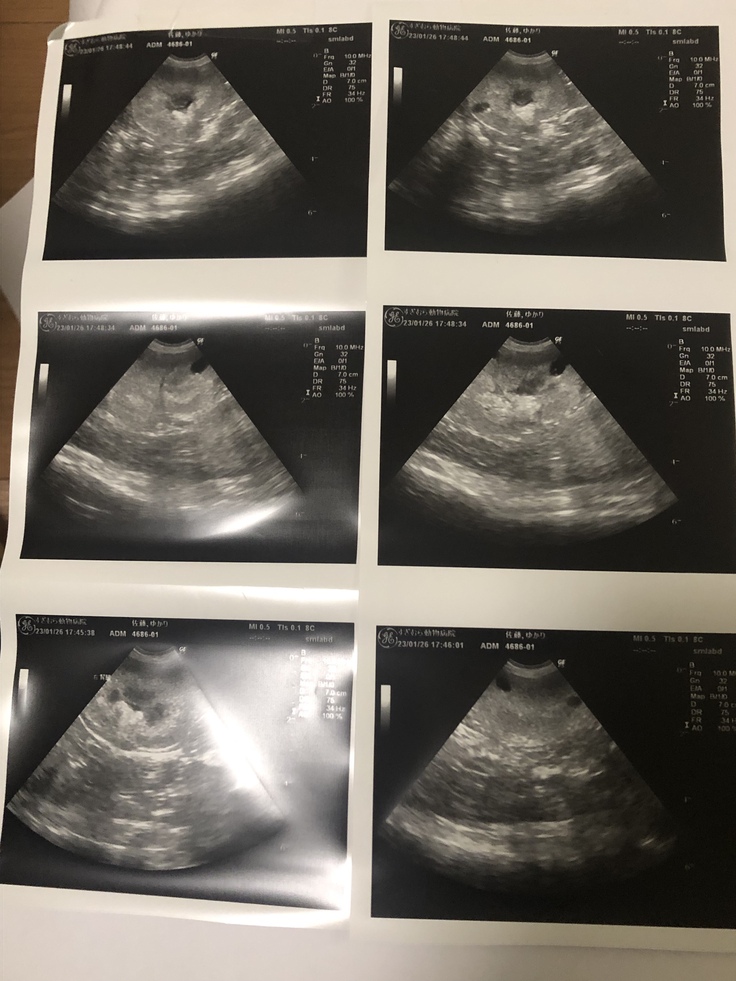

1月中旬の血液検査で腎臓の数値が非常に悪くなっており、1/26に血液検査、レントゲン・エコー検査の結果腎不全のステージ3と診断され腎臓の薬も追加で服薬を開始。また自宅での点滴治療を開始しました。

腎不全の診断書です↓